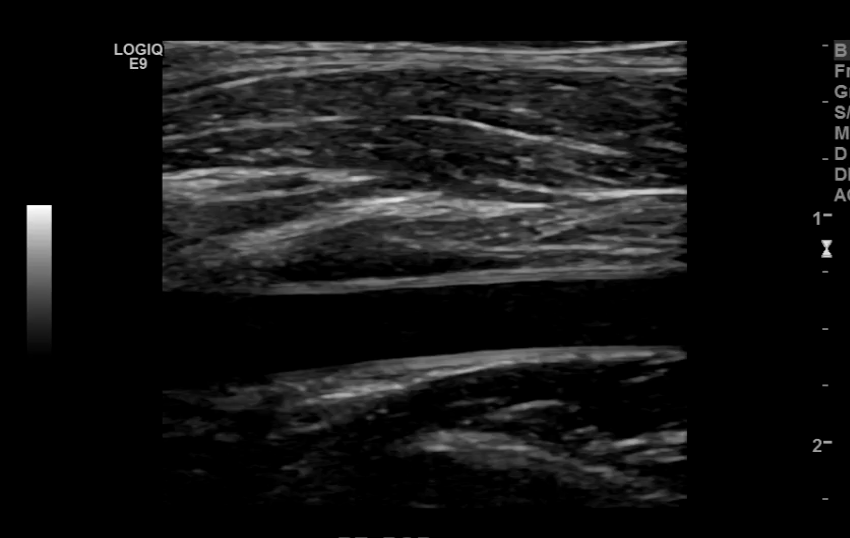

The iliac arteries bifurcate into external and internal iliac arteries (EIA and IIA). The EIA continues caudally turning into the common femoral artery (CFA) which further bifurcates into superficial femoral (SFA) and deep femoral artery (aka profunda femoris). The SFA then converts into the popliteal artery which bifurcates into the tibioperoneal trunk and anterior tibial artery (ATA). The tibioperoneal trunk bifurcates into posterior tibial artery (PTA) and the peroneal artery. The anterior tibial artery descends further to become the dorsalis pedis artery (DPA).

Anterior Tibial Artery